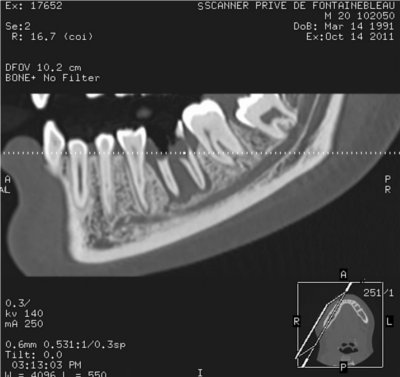

- Pour le scanner, vous serez allongé sur une table qui se déplacera à l’intérieur d’un anneau. Vous devrez serrer entre vos dents un coton afin que les dents ne se chevauchent pas.

Les nouvelles générations de scanner permettent de faire une acquisition d’un volume global d’une partie du corps et de travailler à l’intérieur de ce volume en isolant une structure anatomique donnée et de l’explorer dans tous les plans de l’espace.

Grace à la technique de seuillage il est possible de dissocier progressivement les dents des structures osseuses environnantes dans le volume donné.